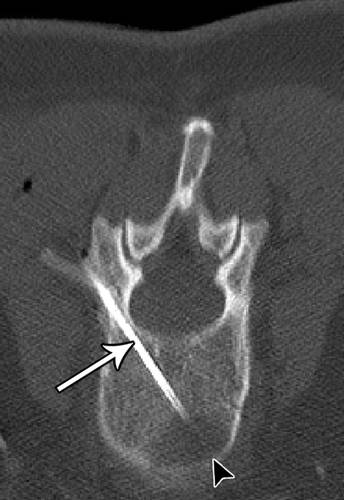

脊柱

典型地,使用通过椎弓根的方法对椎体损伤进行活组织检查(图16))。然而,如果病变的震中不能通过椎弓根进入,可考虑腰椎椎间盘入路(图17)。向软组织中注射盐水可以用于使组织远离脊柱移位,并使相邻的肺远离针的路径(图18A,18B)。

![]()

16 - 55岁的妇女转移性乳腺癌。椎弓根溶解病变(箭头)使用经椎弓根方法。